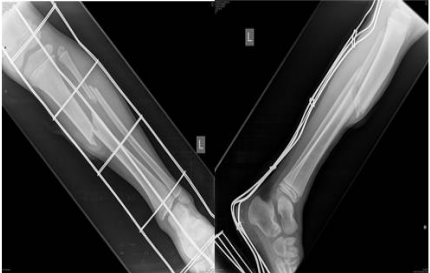

Figure 4&5: Tibial fracture with dislocation.

Figure 6: Control X-ray after conservative immobilization treatment.